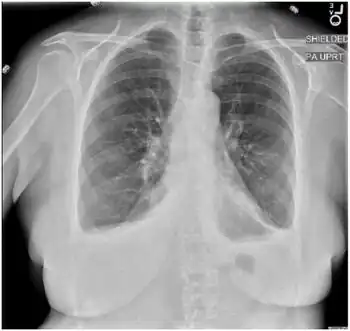

Radiograph of chest shows small bilateral pleural effusions with no airspace disease

In a prior case of Bornholm disease the laboratory results showed the white blood cell count, hemoglobin, hematocrit, creatinine, liver function test (LFT), troponin, and creatine kinase (CK) were all within normal limits. The chest x-ray showed bilateral pleural effusions which resolved after infection. The erythrocyte sedimentation rate (ESR) and C-reactive protein (CRP) levels were found to be elevated. The electrocardiogram (EKG) did not show any abnormalities related to ischemia.[10]